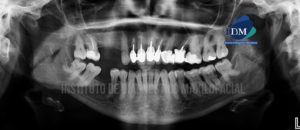

Paciente de sexo femenino de 50 años de edad acude al Instituto de Diagnóstico Maxilofacial para evaluación imagenológica de la pieza 12. A la evaluación

Paciente de sexo femenino de 45 años de edad acude al Instituto de Diagnóstico Maxilofacial para evaluación imagenológica integral. A la evaluación de la radiografía